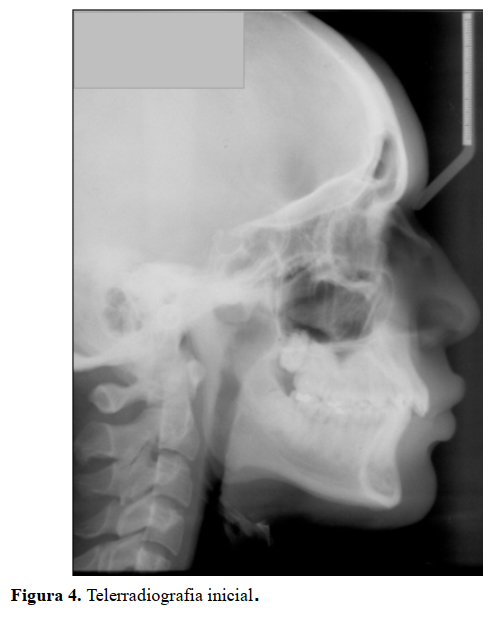

Na radiografia panorâmica foi observada a presença de angulação distal das raízes dos caninos inferiores. Foi possível notar ainda a presença dos dentes inclusos 18 (terceiro molar superior direito), 28 (terceiro molar superior esquerdo) 38 (terceiro molar inferior direito) e 48 (terceiro molar inferior direito), e as restaurações nos dentes posteriores. Não foi notada nenhuma alteração significante nas estruturas adjacentes aos dentes (Figura 3).